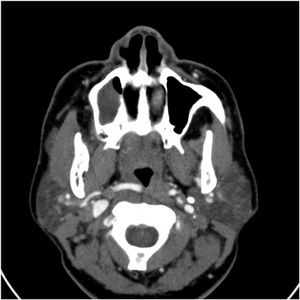

A 57-year-old female presents to the emergency department with dysphagia and reports her throat is “closing up.” On physical exam, there are no palpable masses appreciated along the neck, and the thyroid descends along the midline on swallowing and is noted to be slightly enlarged.